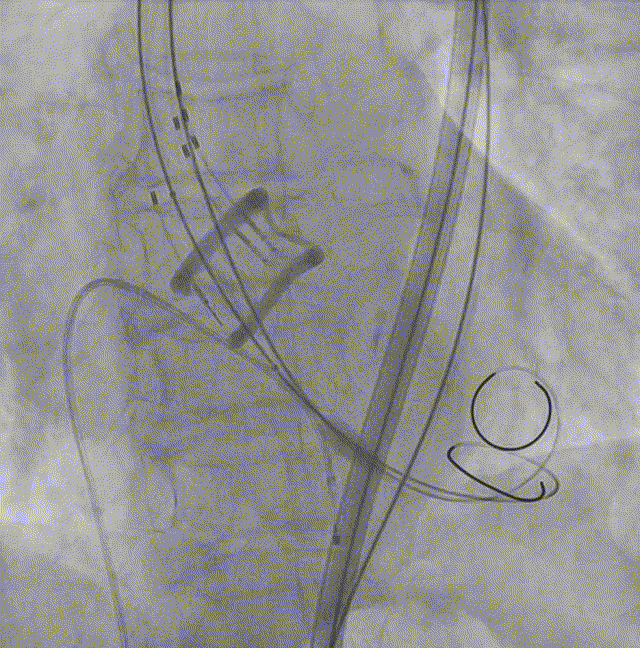

6. 20mm球囊预扩张;

球囊预扩张

7. Silara A-23mm瓣膜过弓和跨瓣;

8. Silara A-23瓣膜左心室初步释放,瓣膜功能良好(不需要左心室快速起搏);

瓣膜释放